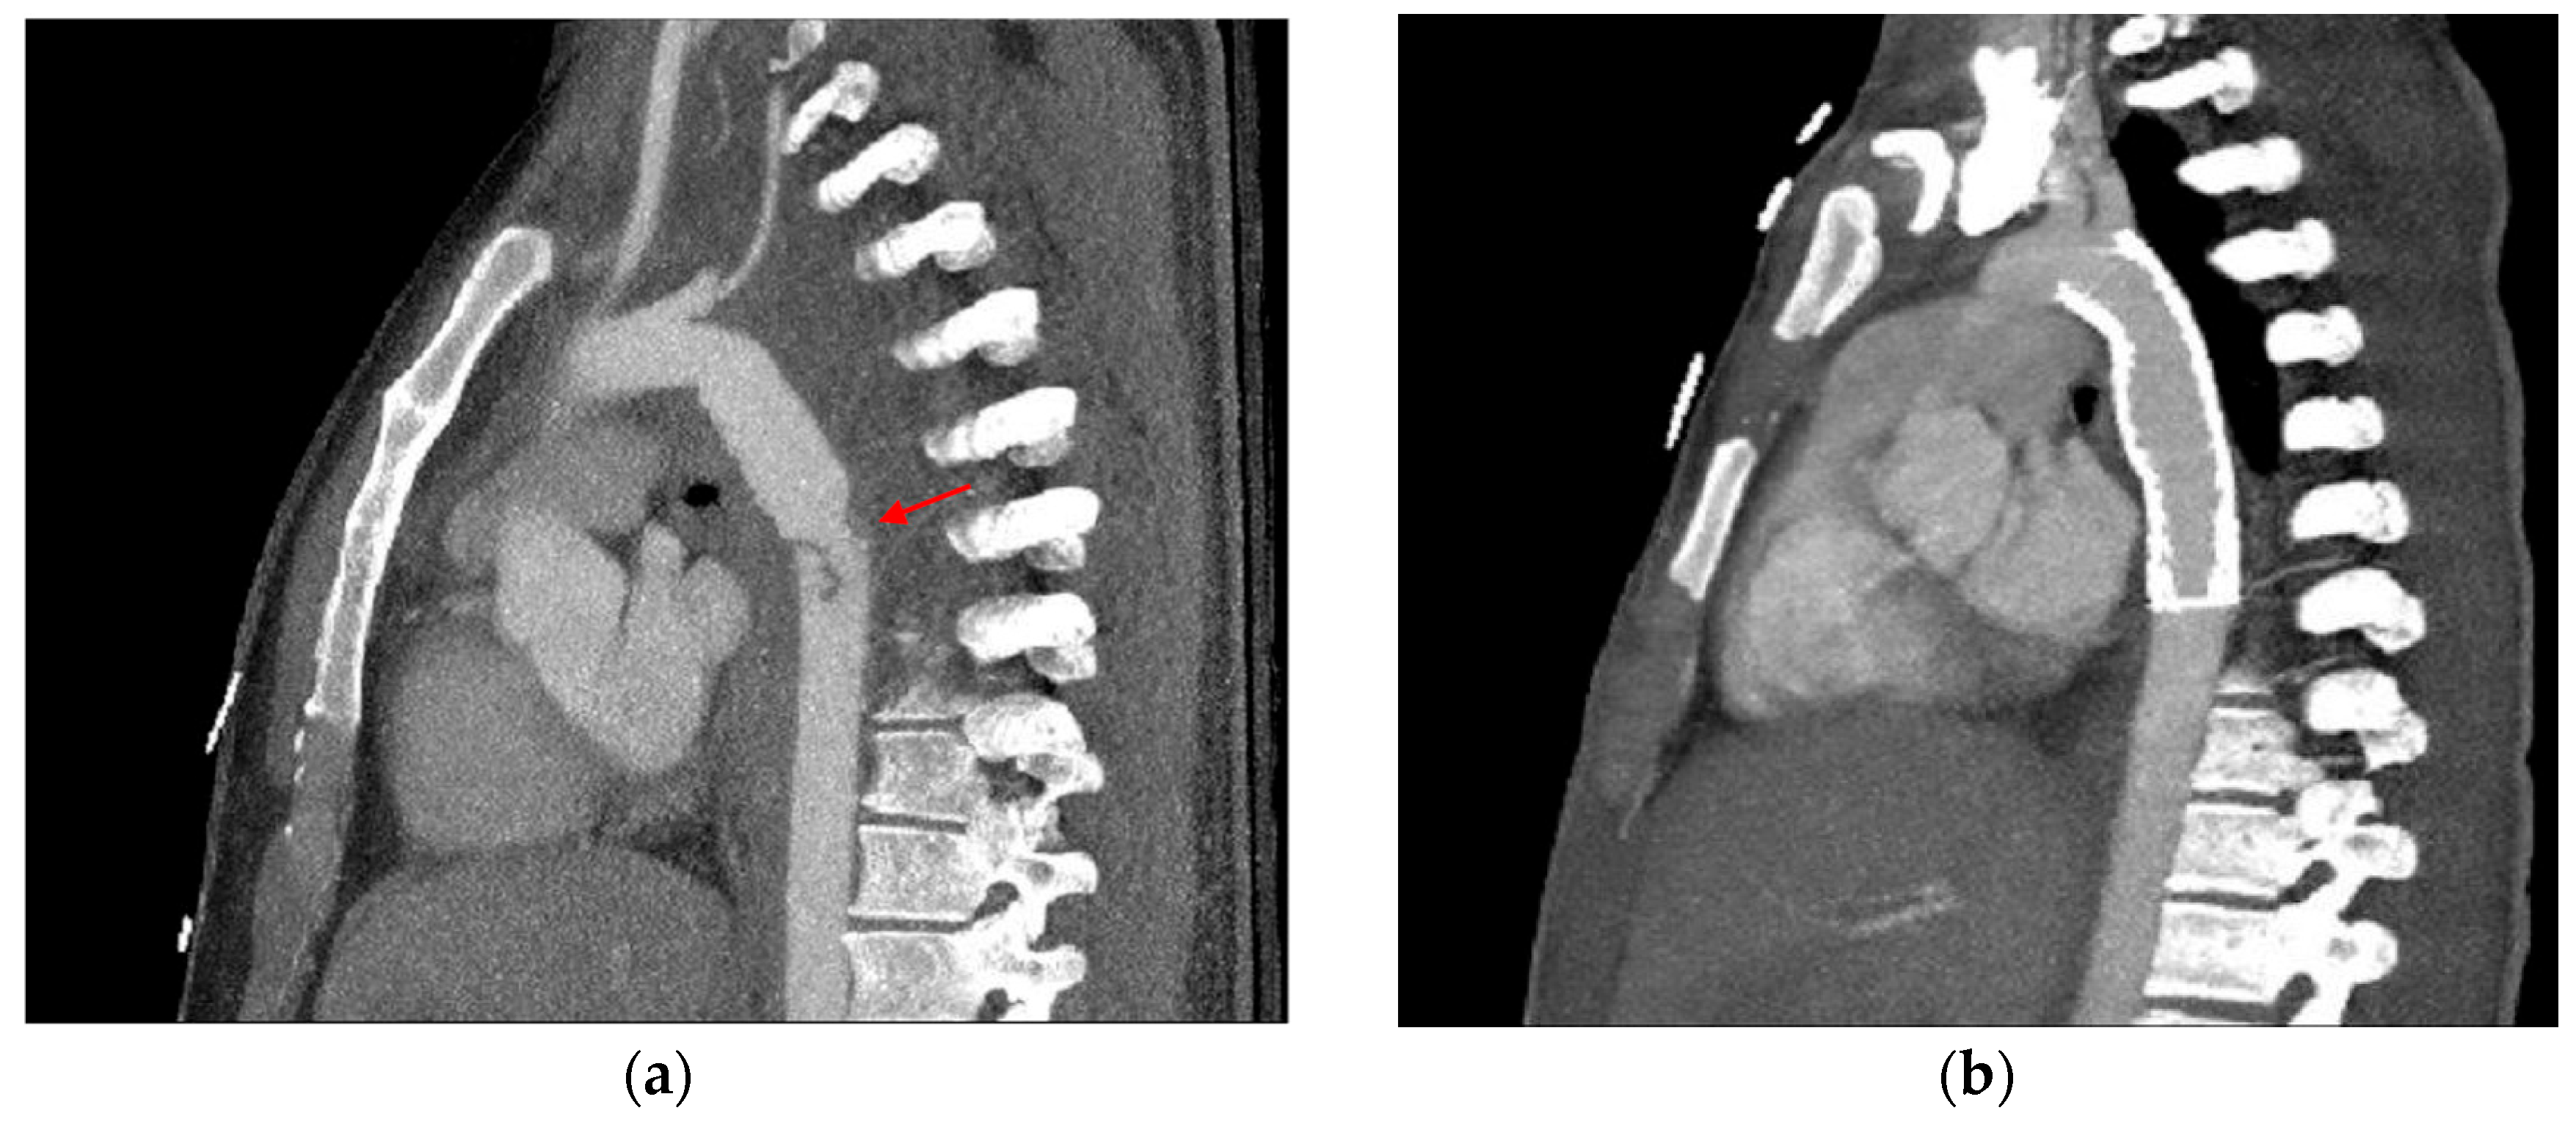

3.1.3. Mimics and Anatomic Variations

3.1.5. CT Angiography Artifacts